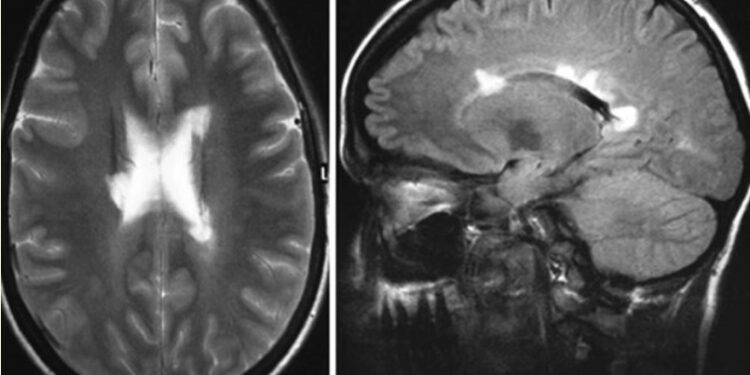

МРТ черепа продемонстрировала несколько областей повышенного сигнала в перивентрикулярном распределении, что соответствует демиелинизации (фигура 1).

(A) Осевые Т2-взвешенные и (B) сагиттальные последовательности магнитно-резонансной томографии с восстановлением инверсии, ослабленные инверсией, показывают перивентрикулярные гиперинтенсивные поражения, типичные для рассеянного склероза.